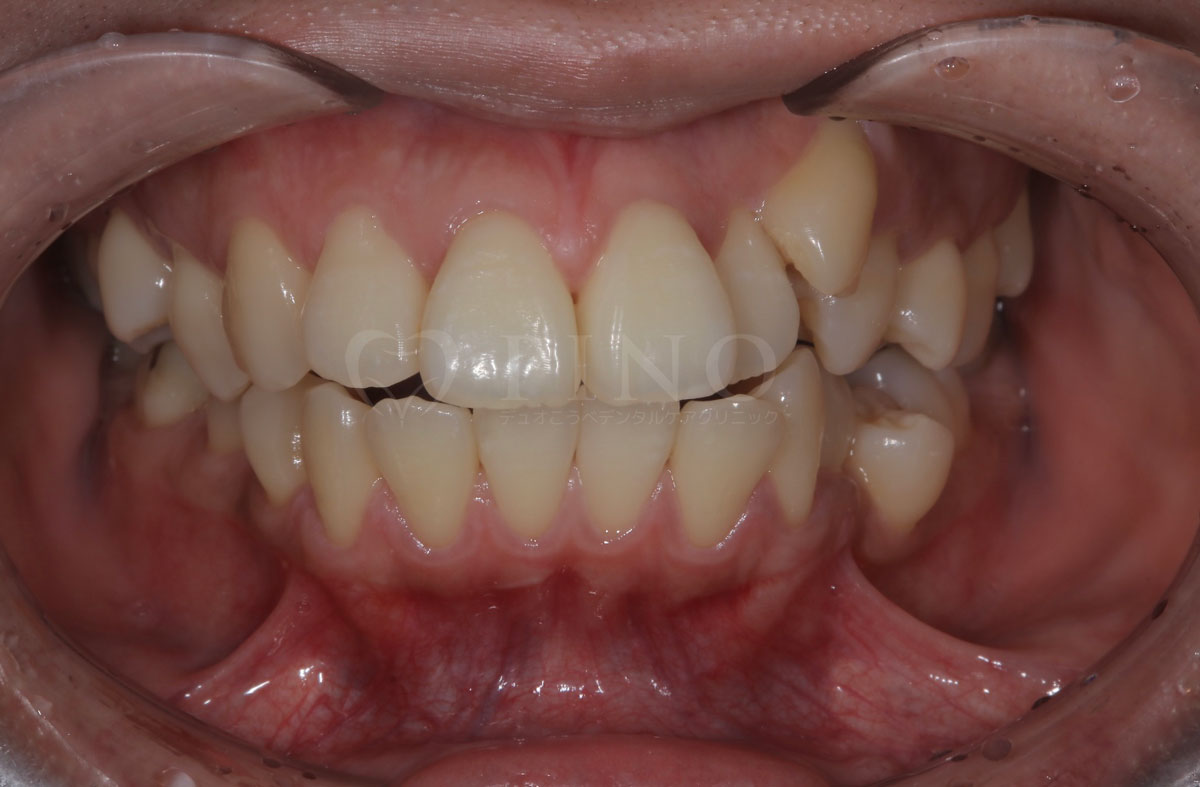

症例4:噛み合わせが深く、下の歯が見えないのが気になる(10代女性)

主訴 噛み合わせが深い、下の歯が見えない 診断名 過蓋咬合(かがいこうごう) 治療方法 マウスピース全顎矯正 抜歯 なし オルソパルス なし 治療期間 1年1ヶ月 費用 746,000円 副作用・注意点 矯正後の後戻りを防ぐためリテーナーの使用が必要となる -